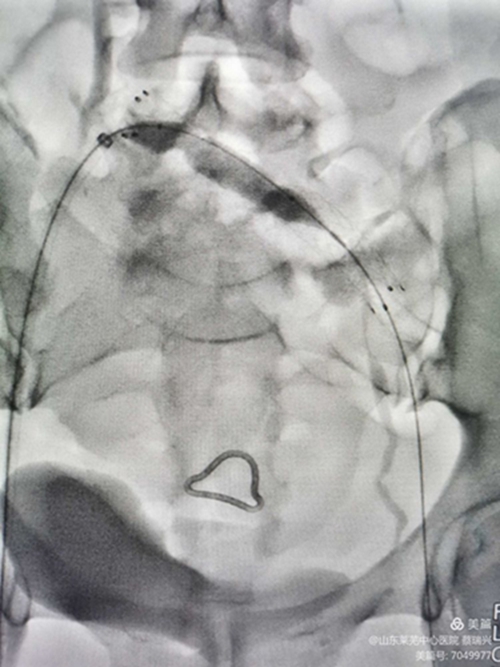

男性,81歲,左下肢腫脹4天入院,行走不至百米,疼痛,便要休息,嚴(yán)重功能障礙。左下肢I(xiàn)II度水腫,脹力高。腳踝部有淤血斑。彩超示,左下肢深靜脈諸段屬支血流通暢,速度慢。髂總靜脈觀察不清。認(rèn)為還是髂總有問題,行造影。取左腘靜脈入路,造影證實(shí)左髂總靜脈閉塞,開通后留置溶栓導(dǎo)管4天。給予左髂總靜脈支架成形術(shù)。溶栓導(dǎo)管造影證實(shí),左髂總?cè)杂兄囟泉M窄,血流不暢,易再閉。

閉塞前改變